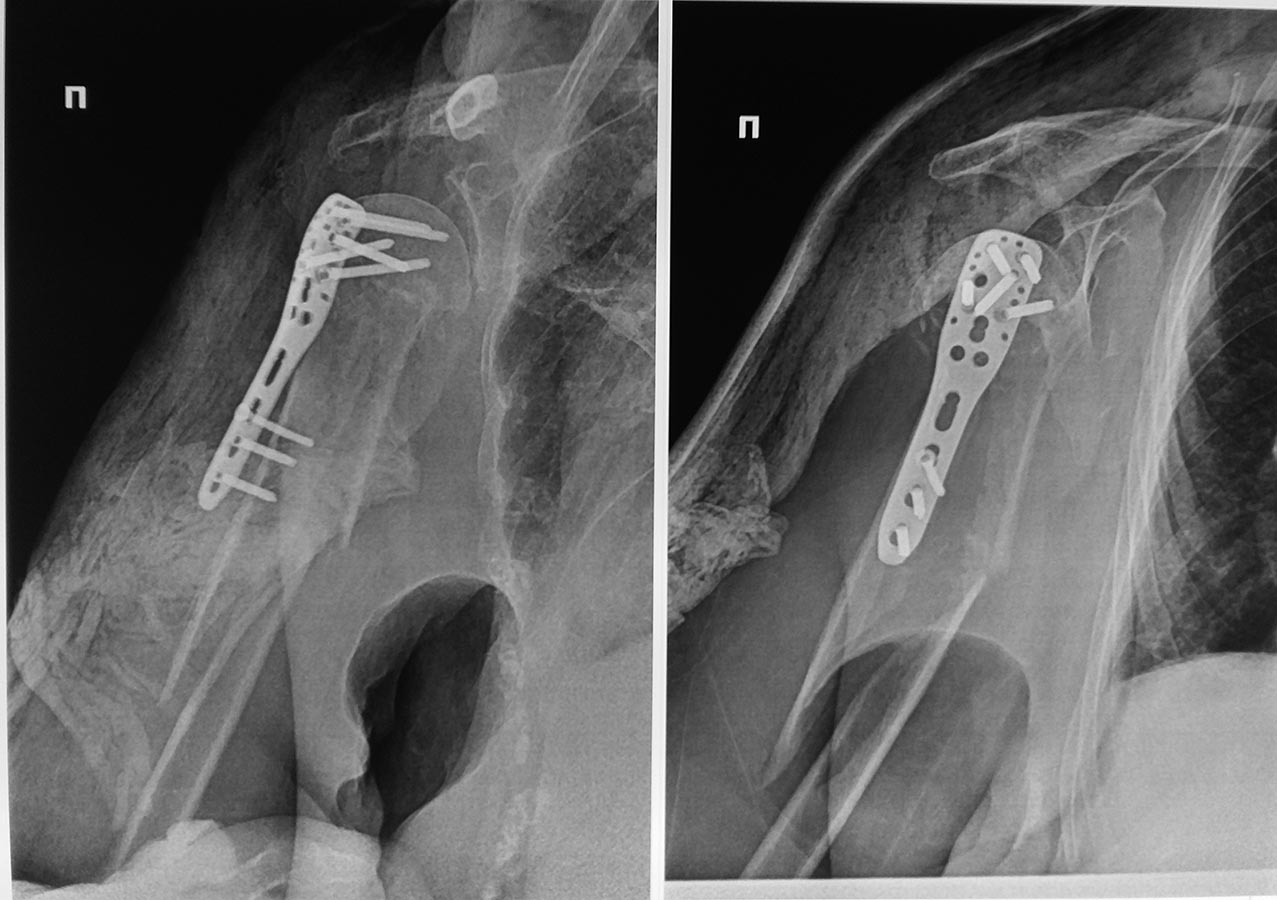

Таков результат. Раны зажили первично. Пациентка выписана без иммобилизации. Буду наблюдать в динамике. Жду комментариев.Коллеги. Спасибо всем за советы.

А можно более развернуто? Что как сделали?

И снимки в других проекциях увидеть бы.

По этому снимку не радует большой диастаз.